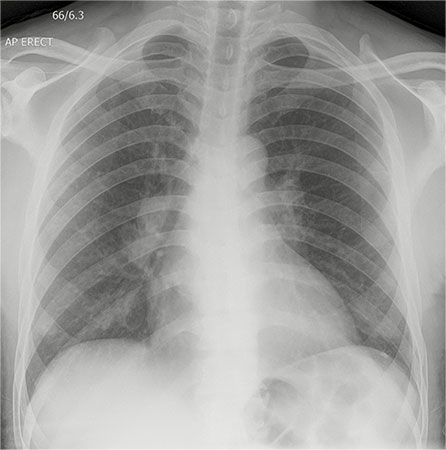

Olgu 1: 63 yaşında erkek, 2 haftadır süren, kuru öksürük, gece terlemesi, kilo kaybı ve altı gün önce tüm vücutta yaygın döküntü şikayetleri ile başvurdu. Tetkiklerinde normositer anemi (hemoglobin 9.5 g / dL), anti HIV (+), CD4 sayısı 5 hücre/ μL idi. Fizik muayenede, ışığa duyarlı gövde ve ekstremitede eritemli papüller ve püstüller mevcuttu (Resim 1). Akciğer grafisinde bilateral hiler lenfadenopati ve bilateral nodüler pulmoner infiltrasyon saptandı(Resim 2). Deri punch biyopsisinde dermise uzanan mikro apse formasyonu ile subkorneal püstül, Ziehl-Neelsen boyamasında aside dirençli basil tespit edildi (Resim 3).

Resim 2. |